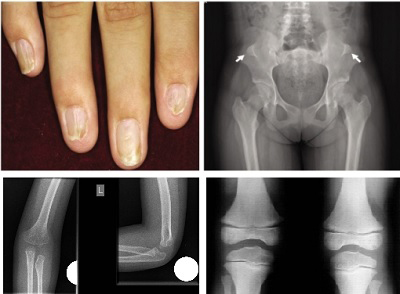

Tırnaklar: Hastaların %98'inde el tırnaklarında simetrik tutulum görülür. Tırnaklar tamamen olmayabilir (anonşi), az gelişmiş olabilir (hiponişi), kaşık şeklinde olabilir (koilonişi) veya kolayca kırılabilir (onikorreksis). Tutulum genellikle başparmakta daha şiddetlidir. Tırnak dibindeki lunulanın V şeklinde olması bu sendrom için tipik bir bulgudur. El içi ve ayak tabanında aşırı terleme (hiperhidrozis) de mevcuttur.

Dirsek Eklemi: Dirsek eklemini oluşturan kemiklerin (humerus ve radius) yetersiz gelişimi (hipoplazi) %90 oranında görülür.

Diz Eklemi: Diz kapağının (patella) olmaması ve dizde kalıcı çıkıklar %90 oranında görülür.

Kalça Kemikleri: Her iki kalça kemiğinde de iliak boynuzlar adı verilen kemiksi çıkıntılar %30 oranında bulunur.